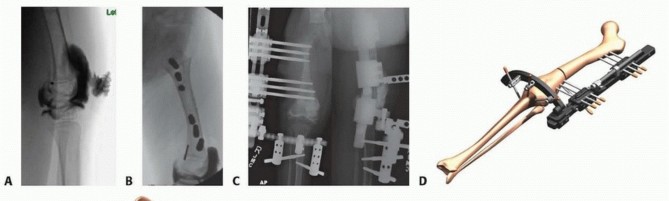

releases that were addressed during a previous superhip or superknee procedure do not need to be repeated. Illustration 13 for Treatment for Congenital Femoral Deficiency: What You Need to Know Illustration 14 for Treatment for Congenital Femoral Deficiency: What You Need to Know Illustration 15 for Treatment for Congenital Femoral Deficiency: What You Need to Know FIG 7 • A. Patient with Paley type 3b CFD with severe leg length difference and knee flexion contracture. B. Clinical photo just prior to rotationplasty. C. Radiograph after Paley modified Brown rotationplasty. D. Photograph showing the appearance after rotationplasty. E,F. Side views showing knee flexed (ankle at neutral) and knee extended (ankle plantar flexed). _ Lengthening via External Fixators *_ Femoral lengthening with an external fixator can be performed with various devices. The essential principle of lengthening with external fixation is to stabilize the knee during lengthening while allowing for knee motion. This is accomplished by using hinges and external fixation of the tibia. From 1987 to 2000, the author used only the Ilizarov apparatus with fixation across the knee joint with a hinge for all CFD lengthening cases. This method has previously been described.9 A monolateral external fixator was not used because it could not articulate across the knee joint. From 2000 to 2009, the author modified the Orthofix Limb Reconstruction System (LRS) rail (Orthofix, Inc., McKinney, TX) with the Sheffield Ring Fixation System arch (Orthofix) to articulate across the knee with fixation to the tibia. This method was used for all CFD cases between January 2000 and May 2009. From 2009 to the present, the author designed a special external fixator specifically for articulated spanning of the hip and knee joints. The Modular Rail System (Smith & Nephew, Memphis, TN) has been used in all CFD cases since June 1, 2009.

2. Femoral Lengthening of Type 1 Congenital Femoral Deficiency: Orthofix Fixator Technique Preparatory Surgery If there are no indications for hip or knee surgery, the fascia lata and rectus femoris proximally and the iliotibial band and biceps tendon distally should be released at the time of the lengthening surgery.

If these tissues were released with a previous Dega, superhip, or superknee procedure, there is no need to do any soft tissue releases. Placement of Femoral Fixator An arthrogram of the involved knee is obtained under fluoroscopy. In the lateral view, the femoral condyles are rotated until they superimpose each other. This is considered a “true lateral of the knee.” (Note that this is not the patella-forward position— actually, the patella will be externally rotated approximately 10 degrees in this position.)

The center of knee rotation is identified. The center of rotation is the intersection of the posterior cortical line and the distal femoral physeal line.

A 2-mm Steinmann pin is inserted into the distal femoral physis at the center of rotation and parallel to the distal femoral joint line in the frontal plane ( TECH FIG 10A ). A half-pin is inserted into the femur at its proximal end parallel to this hinge-axis pin. To accurately place the half-pin, use the cannulated drill technique. Insert a wire into the femur and check if it is in the correct location with the image intensifier. Then over drill it with a cannulated drill. The half-pin is then inserted in a perfect position. Half-pins placed in the anterior half of the femoral diaphysis can result in a fracture either during the lengthening process or after frame removal. The preconstructed modular rail system (MRS) (Smith & Nephew, Memphis, TN) is applied so that distally the Steinmann pin goes through the cannulated hinge bolt and proximally the half-pins goes through the proximal clamp. The most distal half-pin is placed one hole proximal and anterior to the knee axis reference wire. At this point, the position of the hinge axis is a fixed point to the initial distal half-pin. The additional half-pins are placed proximal and distal. Three frontal plane half-pins should be placed in each segment ( TECH FIG 10B ). The osteotomy is made immediately proximal to the distal pin group. This is done through a 1-cm lateral incision, followed by multiple drill holes with an osteotome, followed by completion of the osteotomy with an osteotome. If concurrent distal valgus deformity is being corrected, the proximal and distal pins are placed at angles to each other and the osteotomy performed after there are two proximal and two distal pins. The rail is placed only after the deformity is corrected. The deformity is corrected acutely and the rest of the fixation is as for the underformed bone. The external fixation is completed with insertion of two AP pins ( TECH FIG 10C-E ). Illustration 50 for Treatment for Congenital Femoral Deficiency: What You Need to Know Illustration 51 for Treatment for Congenital Femoral Deficiency: What You Need to Know TECH FIG 10 • A. Steinmann pin is inserted into the distal femoral physis at the center of rotation of the knee with a knee arthrogram lining up the two posterior femoral condyles. B. The other half pins are placed parallel to the Steinmann pin. The external fixator is used as a template. C. The external fixator is removed and the osteotomy performed. The fixator is then reapplied to the femur and the tibial frame and pins added. D. The MRS with knee hinge and articulated fixation to the tibia from the femur. E. The MRS with hip and knee hinge with articulated fixation to the pelvis and tibia from the femur.Placement of Tibial Fixator A distal rail segment is used to suspend a floating arch. The tibial fixation is attached to this arch. A single-hole Ilizarov cube is placed on the arch, and an AP half-pin is placed in the proximal tibia. The knee should be in full extension and reduced. After the first half-pin is inserted into the tibia, the hinge is tested with gentle ROM of the knee. If the motion is smooth, a drop leg test is performed. The drop leg test consists of lifting the lower extremity off the bed and fully extending the knee. The thigh is supported and the foot dropped. If the knee flexes with no catching or friction, two additional half-pins are placed in the tibia. If there is friction during the drop leg test, connection to the pin needs to be adjusted (eg, fix it in flexion first). After the adjustment, the drop leg test is repeated until knee ROM is smooth, with no friction. The floating arch is not connected to the rail. It therefore does not impede growth of the distal femoral and proximal tibial physes. A knee extension bar is built using Ilizarov parts between the rail and the arch. This knee extension bar can be removed to allow knee motion. It should be used all night and part time during the day to prevent knee flexion contracture. If hip stabilization is required, a hip hinge clamp is used. It is centered on the center of the femoral head. Three pins are placed in the pelvis and fixed with an arch (see TECH FIG 8E ). At the conclusion of the procedure, Botox, 10 units per kilogram of body weight, is injected into the proximal quadriceps using multiple injection sites. This is to reduce quadriceps muscle spasms and pain during knee flexion stretches.